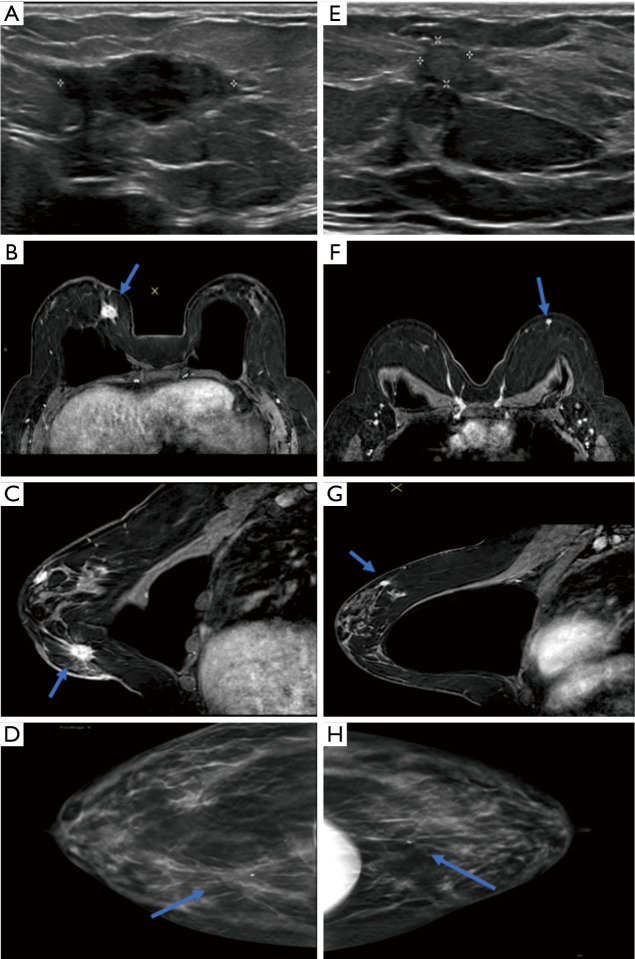

Case description: This is a case report of a 34-year-old female with a history of bilateral silicone implant placement who presented with bilateral breast masses. She reported a 6-month history of a 1-cm firm, palpable mass in the right breast without associated pain or growth. She had a family history of breast, pancreatic, and prostate cancer but no significant past medical history. Ultrasound-guided biopsy of the right breast and magnetic resonance imaging (MRI)-guided biopsy of the left breast both revealed fibromatoses. She underwent bilateral excisional biopsies and surgical pathology confirmed breast fibromatosis in the background of benign breast tissue with fibrocystic changes. The patient had an uncomplicated post-operative course.